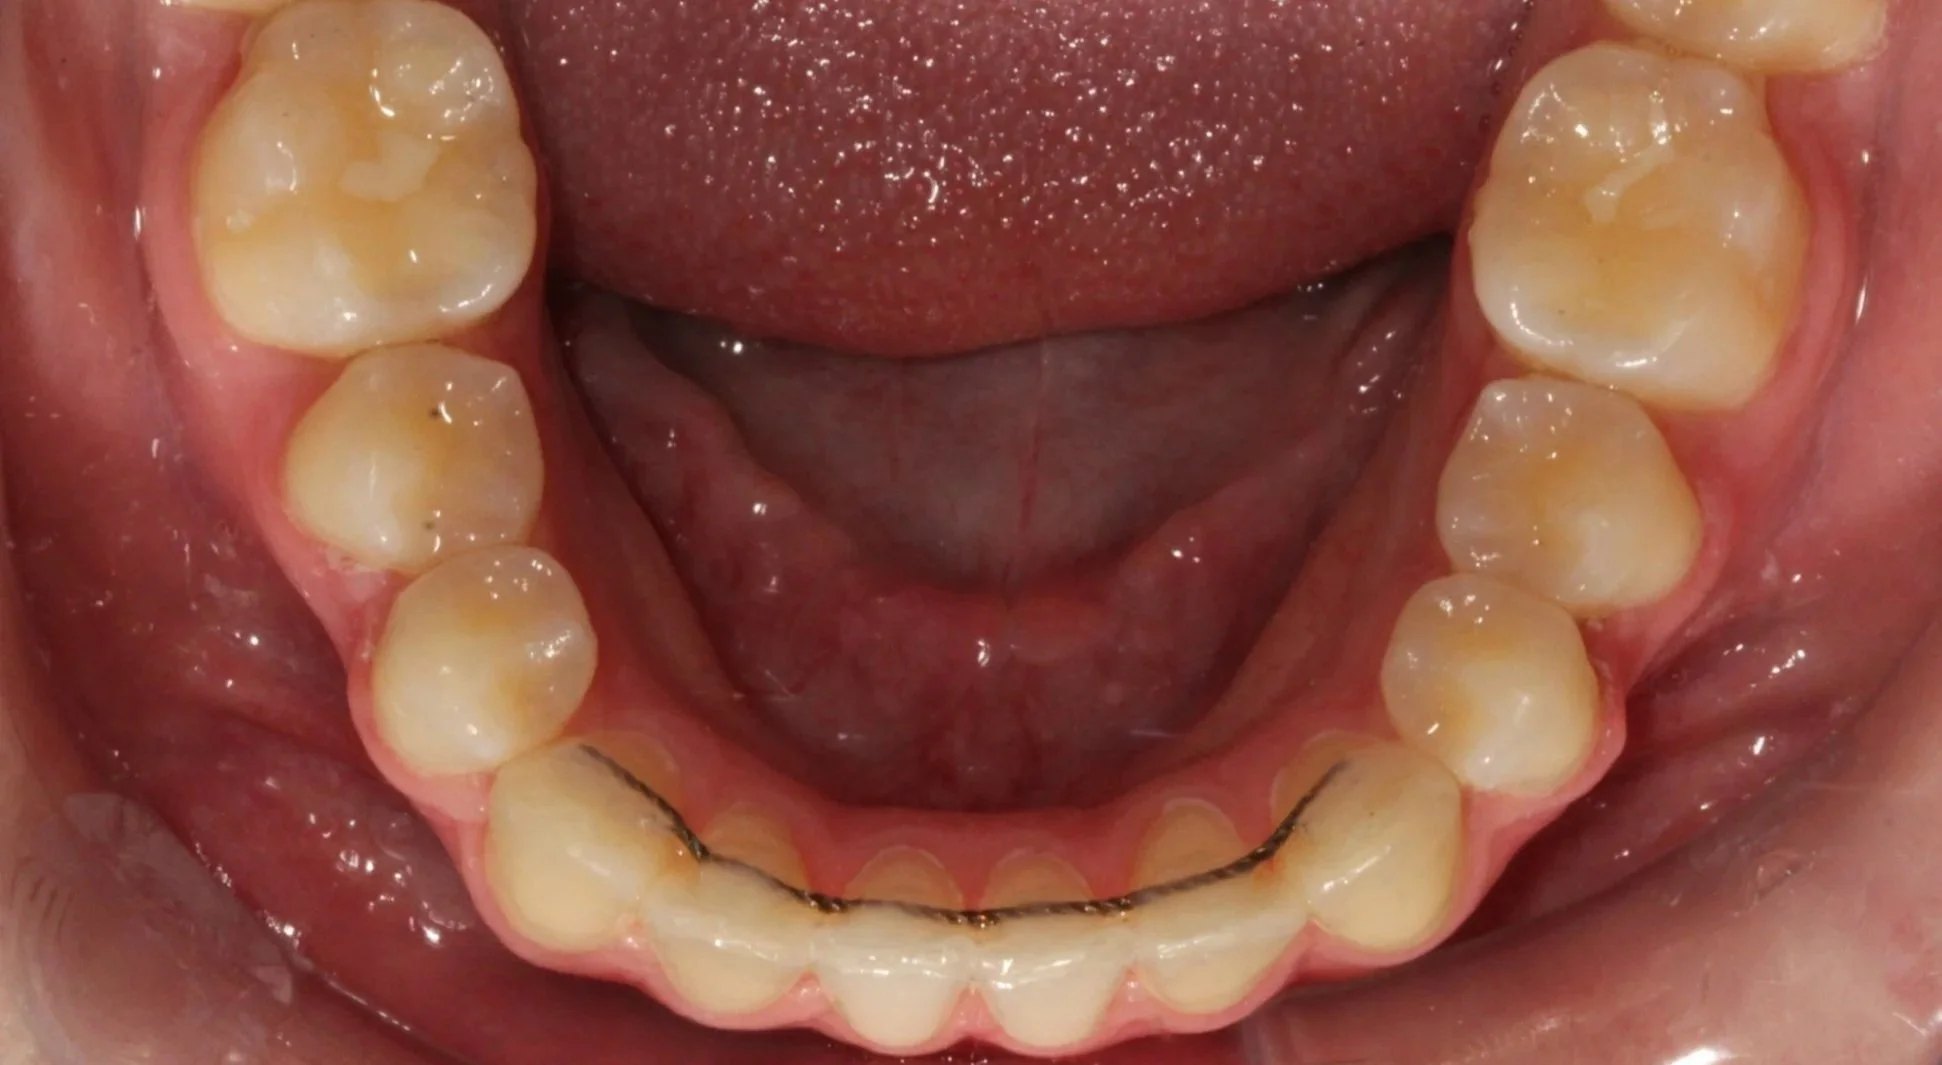

Lingual retainer

Lingual

A Lingual Retainer is a braided stainless steel wire that connects to the lingual (back) surfaces of the front teeth. Composite resin (dental restorative material) is used to adhere the appliance to the teeth. The Lingual Retainer is used to maintain a previous orthodontic result or to simply prevent undesirable movement of the teeth. We encourage patients to clean the appliance with toothpaste and a toothbrush each and every time the teeth are brushed. Flossing – threading the floss under the appliance at each point of contact – is advised at least once a day.